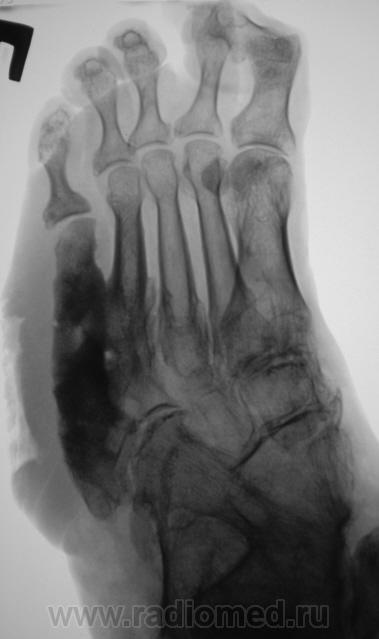

Пациентка направлена на рентгенографию стоп.

Правая стопа.

Направительный диагноз - "Диабетическая ангиопатия".

Некоторые коллеги высказали мнение по поводу наличия остеомиелита.

По правой стопе я бы тоже поставил Гарре, но слева такое вылезает. Может все-таки системное?

Хирург, увидев только одну стопу - правую, левая, еще была в работе, ответственно заявил - "остеогенная саркома"...

Системное поражение, возможно как следствие диабетической ангиопатии;слева V плюсневая кость с прерывистым контуром ( возможно остеонекроз на фоне ангиопатии). Не видел подобного ранее.

Картинка вобрала в себя все, что клинически называют "диабетическая стопа". Здесь последствия и ангиопатии, и нейропатии, и присоединившейся инфекции. По-моему, имеется и трофическая язва. Прямо студенческий случай. Хотя, я тоже ранее таких стоп не видел.